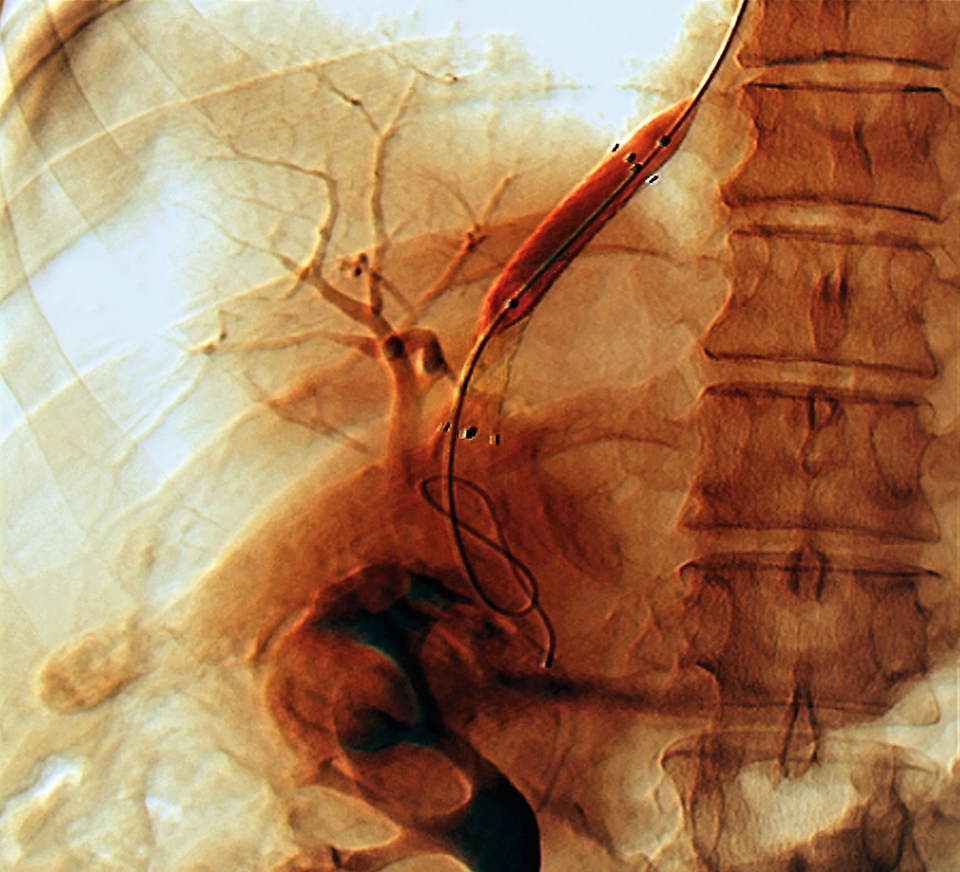

Die Anlage des TIPS erfolgt mittels Katheter über einen transjugulären Zugang. Mithilfe einer Punktionsnadel wird unter sonographischer Kontrolle eine Verbindung zwischen einer Lebervene und einem Ast der Pfortader geschaffen. Durch die Nadel lässt sich ein Führungsdraht bis in die V. mesenterica superior oder die V. lienalis vorschieben. Anschließend wird ein Katheter eingebracht, der eine Kontrastmitteldarstellung der Pfortadergefäße nebst etwaiger Umgehungskreisläufe ebenso ermöglicht wie die Kontrolle der Druckverhältnisse. Schließlich schiebt man einen Stent in den neu geschaffenen Kanal vor und dilatiert so lange mit einem Ballon, bis der portosystemische Druckgradient unter 12 mmHg liegt.

In diesem Fall war eine ösophageale Blutung der Grund für die TIPS-Anlage. In diesem Fall war eine ösophageale Blutung der Grund für die TIPS-Anlage. © Science Photo Library/Zephyr